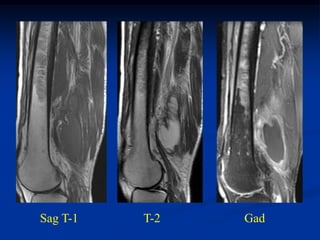

Cor T-1   T-2   Gad

Sag T-1

Gad

Axial T-1   T-2